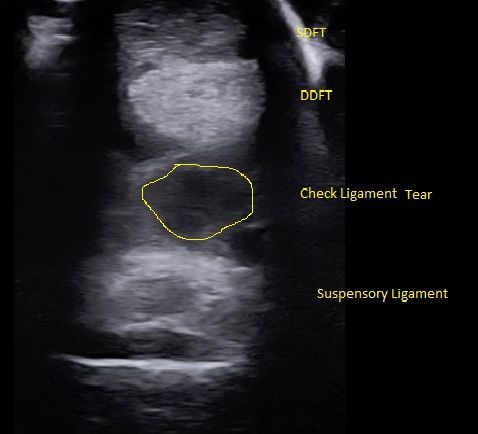

- Digital Ultrasound